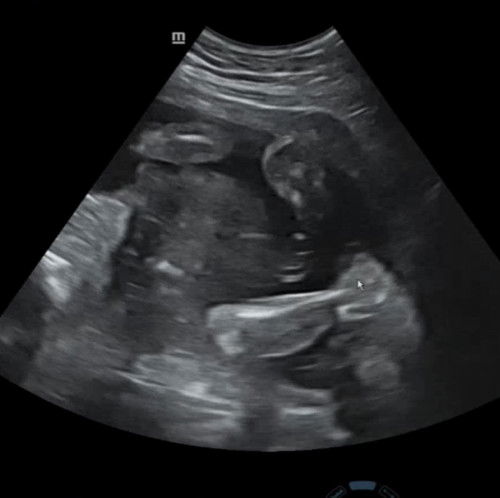

dokternya bilang gimana bun?

Dokternya sii bilang 100 persen cewe katanya